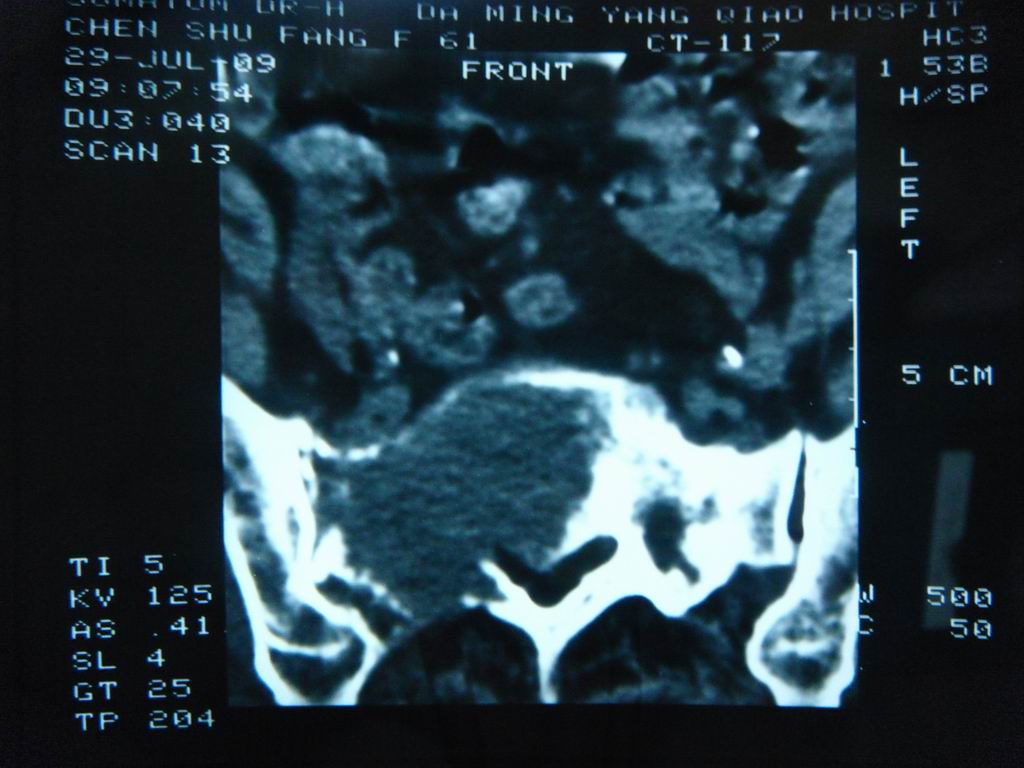

标题: CT21430:女性65岁 乳腺癌术后3年 [打印本页]

标题: CT21430:女性65岁 乳腺癌术后3年

结合病史,考虑骶骨转移瘤,但软组织肿块未突破骨壳,骨巨细胞瘤不能完全排除,骨髓瘤及脊索瘤不考虑。

结合病史,考虑骶骨转移瘤。

结合病史,考虑骶骨转移瘤。其它椎体,如腰5是否有问题呢?

个人感觉骨巨细胞瘤可能性大些。